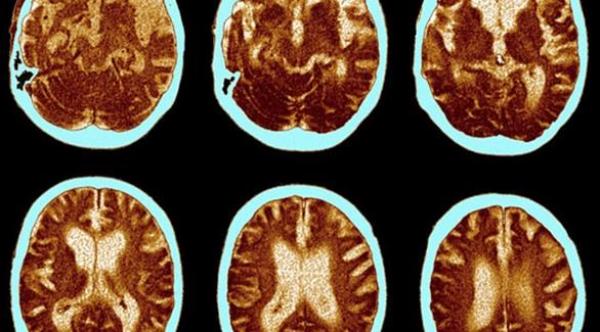

شرح علماء من جامعة كامبريدج البريطانية تشخيص جديد حول كيفية تشكل الخلايا بالدماغ المسببة لمرض الزهايمر، إذ فسروا أن الخلايا تبدأ بالتباطؤ وتشكل لويحات البيتا أميلويد فتتسبّب بتقليص نمو الذاكرة وفقدانها تدريجياً وبالتالي تظهر الأعراض الأولى لهذا المرض.